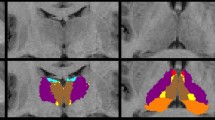

PET image processing

18F-FDG PET images were preprocessed by Statistical Parametric Mapping (SPM8; https://www.fil.ion.ucl.ac.uk/spm), FSL (https://fsl.fmrib.ox.ac.uk/fsl/fslwiki) [19], and FreeSurfer (https://surfer.nmr.mgh.harvard.edu/) [20]. All 18F-FDG PET images of ECTS patients and controls were spatially normalized to an in-house pediatric 18F-FDG PET template, followed by Gaussian smoothing with 6-mm full-width half-maximum (FWHM) [21]. Standardized uptake value ratio (SUVR) was determined to normalize intensities by using cerebellum gray matter as the reference region [22].

In order to validate the hypothesis that the cortical–striatal circuit is the physiologic basis for processing speed in ECTS patients, SPM analysis was first performed to detect all potential metabolic changes across whole brain regions. P value < 0.05 and cluster size > 100 were used as thresholds. Then regional analysis was carried out on region of interests (ROIs) which contained at least 100 continuous voxels of SPM clusters, according to the pediatric PET Desikan–Killiany atlas. The ROIs were also thresholded by gray matter (GM) probability > 60% to reduce the influence of white matter and cerebrospinal fluid retention [23]. The weighted average of regional SUVRs was compared between ECTS patients and controls by two-sample t test, and false positive rate (FDR) was performed to correct multiple comparison. At last, Pearson’s correlation between PSI and mean SUVR was investigated for ECTS patients. Construction of pediatric PET template, Desikan–Killiany atlas, and GM probability map was described in the Supplementary Material S1.